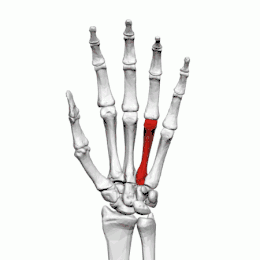

Quatrième métacarpien

Description

Le quatrième métacarpien est plus court que le troisième métacarpien.